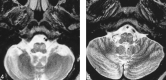

fig 4.

MR examination, 20 months after pontine hemorrhage. Axial T2-weighted fast spin-echo image (TR/TE = 6000/92, echo train length = 12) at the level of the ION shows hypertrophy with hyperintensity of bilateral ION.fig 5. Follow-up axial T2-weighted fast spin-echo image (TR/TE = 5000/105, echo train length = 12) 49 months after hemorrhage into a pontine cavernoma shows hyperintensity in bilateral ION. No evidence of hypertrophy is present